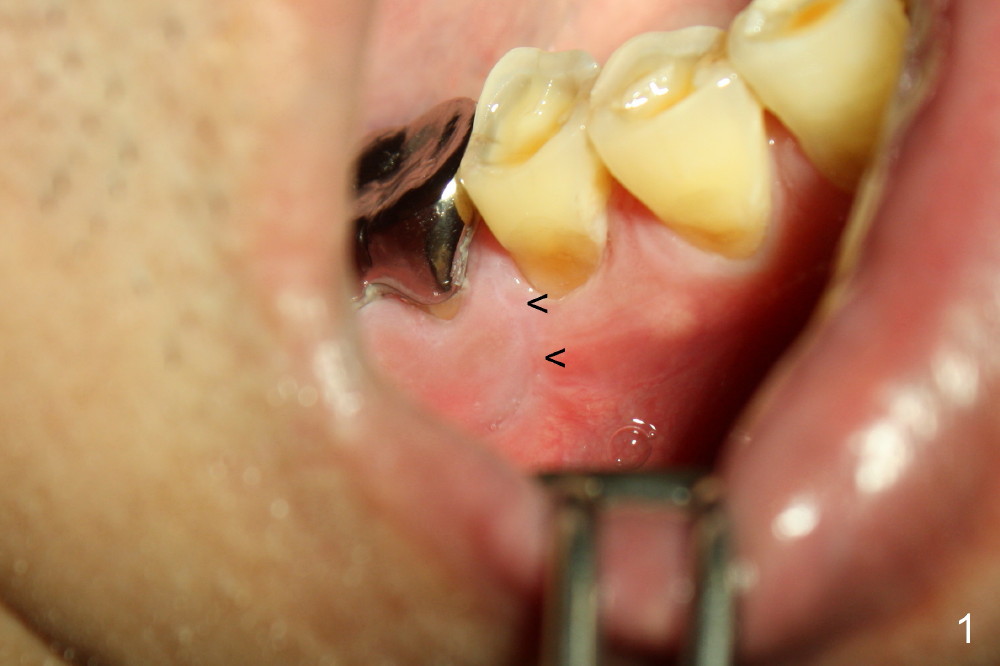

术后二周病人按原计划回来做三十一号牙植牙,病人好像感觉可以,伤口愈合也可以,但是切口的确不对头(图一箭头),根据诸位指点,line angle切口应该是图四红线,对吗?而图四黑线代表原来乳头切口。